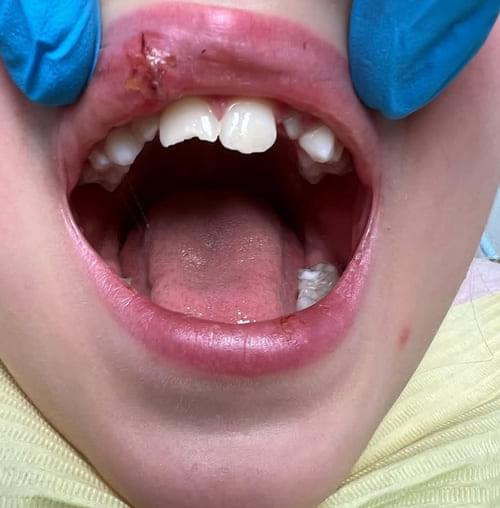

Дівчинка 7 років, перше вересня, гойдалка… Вивих постійного зуба: якщо в такій ситуації зволікати, дитина може втрати постійний зуб назавжди. Батькам порекомендували нас і пацієнти одразу приїхали. Через складність і травматичність процедур вирішено проводити лікування в анестезіологічному супроводі. Зуб поставлений на місце (репонований), проведена хірургічна обробка і ушивання рани губи. Останнє фото через рік після травми: зуб на місці і корінь продовжує розвиватись, губа повністю загоїлась